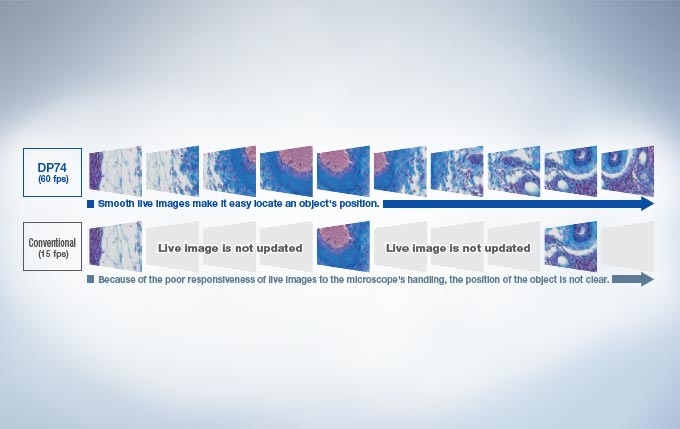

Obtain high-quality images of live specimens higher than FullHD resolution (2.3 million native pixels). The DP74 camera delivers images at a full 60 frames per second. The high frame rate enables users to make observations quickly and easily and capture fast movements in the specimen. The DP74's global shutter eliminates the live image distortion frequently caused by rolling shutter CMOSs.